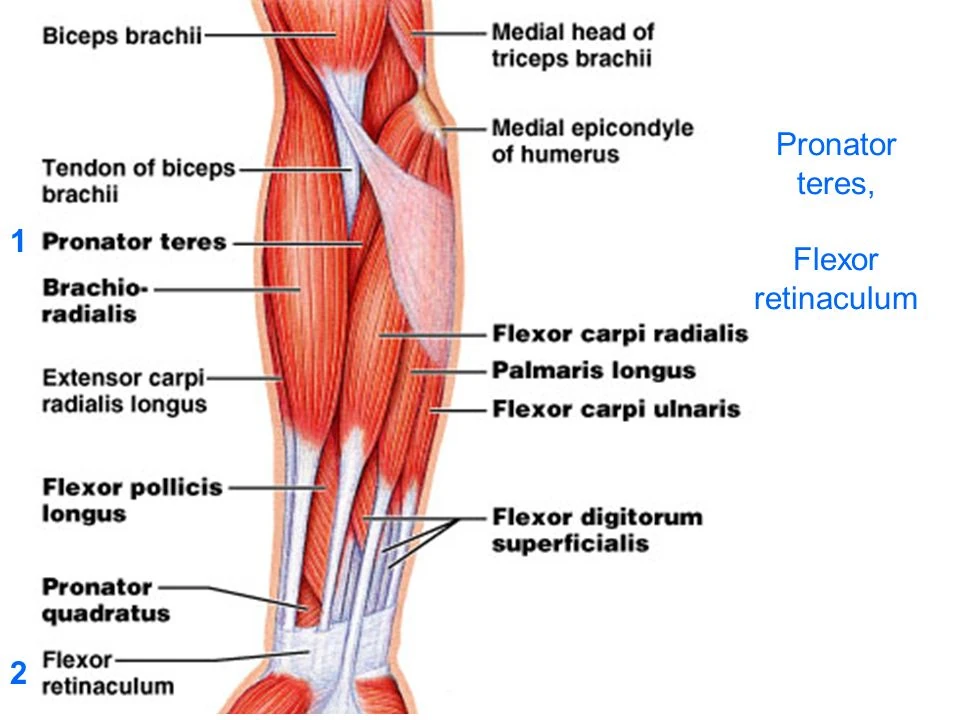

Анатомия мышцы Palmaris Longus